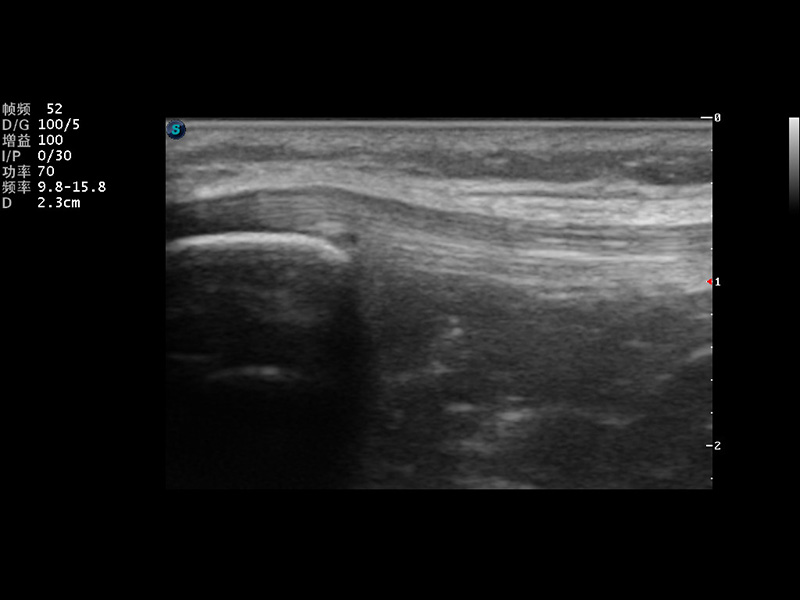

S9便携式彩色多普勒超声诊断仪是milan米兰研发的高端便携彩超设备,外观设计新颖、产品性能卓越。S9在便携超声领域采用了突破传统的触摸屏交互设计,并以先进的软件硬件技术和设计理念,为您带来清晰的图像质量、稳定的工作性能和便捷的操作体验。

μ-Scan微米成像

实时宽景成像